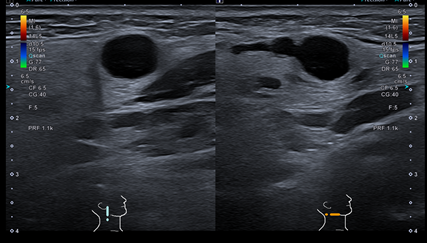

Hallazgos ecográficos

Se realiza ecografía clínica que muestra una imagen redondeada de márgenes regulares hipoecoica de 7,7 mm, sin tabicación y con refuerzo acústico posterior, que parece localizada en la glándula parótida derecha.

Señal doppler dudosa. Junto a esta lesión se visualiza otra de similares características, pero de menor tamaño.